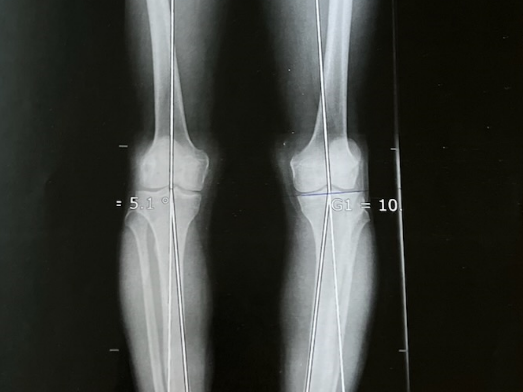

Habituellement, pour un Genu Varum (Jambe « à la lucky luke »), l’ostéotomie tibiale d’ouverture interne avec une hyper-correction en Valgus de 3° à 6° est recommandée. L’ostéotomie tibiale de fermeture externe est une technique difficile, avec des risques de lésions neurologique (Nerf sciatique poplité externe).

Pour le Genu Valgum (Jambe en X), il est préférable de réaliser une ostéotomie tibiale de fermeture interne. Il n’y a pas de consensus sur le degré de correction à obtenir. Généralement, en post-opératoire, l’objectif est d’obtenir un membre normo-axé (HKA = 180°).

En cas de déformation mixte ou si la déformation est supérieure à 10° (HKA<170° ou HKA>170°), l’ostéotomie est très souvent double (fémorale et tibiale). Par exemple, pour le Genu Varum, il est recommandé de réaliser une ouverture tibiale interne et une fermeture fémorale externe.